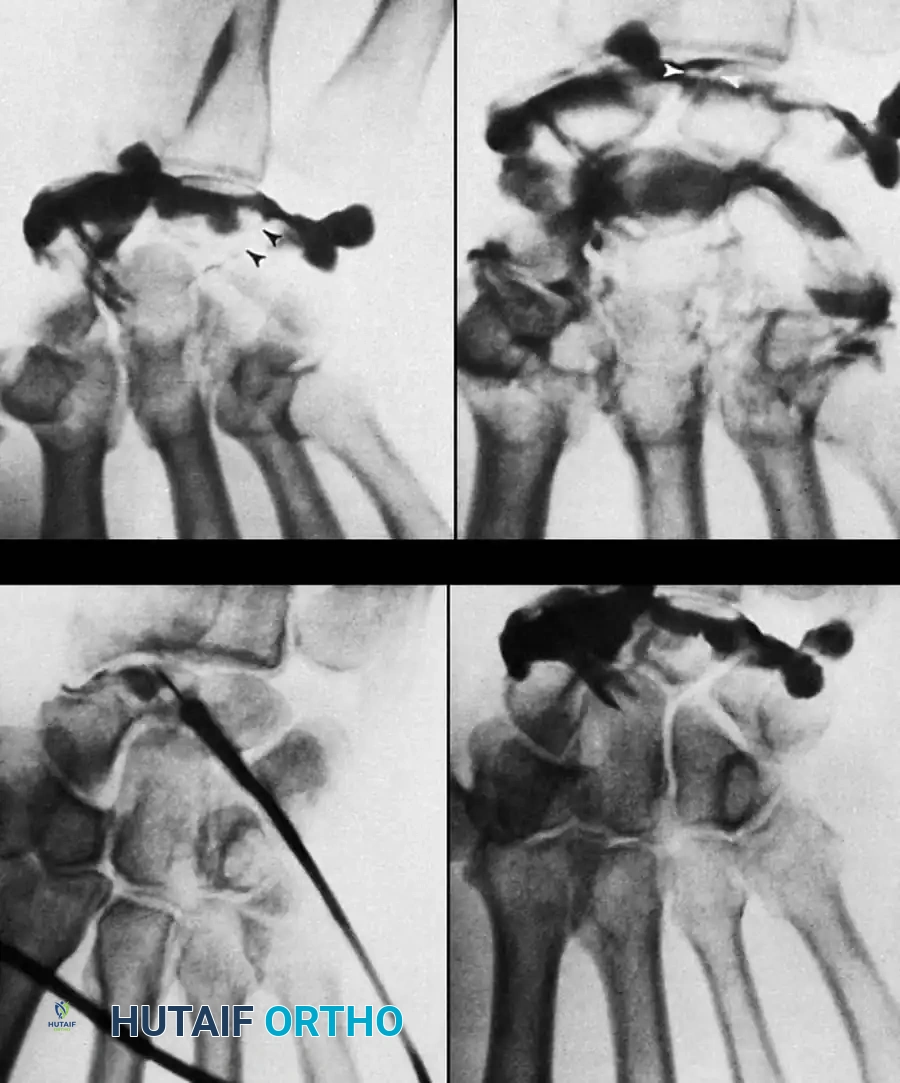

Wrist Arthrography

While largely supplanted by MR Arthrography, traditional triple-injection wrist arthrography remains a powerful dynamic tool. Contrast is injected sequentially into the radiocarpal, midcarpal, and distal radioulnar joints under fluoroscopic guidance.

During the procedure, the flow of contrast is monitored. For example, if contrast injected into the radiocarpal joint passes into the midcarpal joint between the lunate and triquetrum during ulnar deviation, it definitively indicates a full-thickness lunotriquetral ligament tear.

DIAGNOSIS OF WRIST CONDITIONS Surgical Diagram

Pitfall: Contrast material can rapidly fill the midcarpal joints, making it difficult to distinguish whether the scapholunate or lunotriquetral ligament is the primary source of the leak. Fluoroscopic spot viewing during the active injection phase is critical to identify the exact site of contrast extravasation before the entire joint space is obscured.